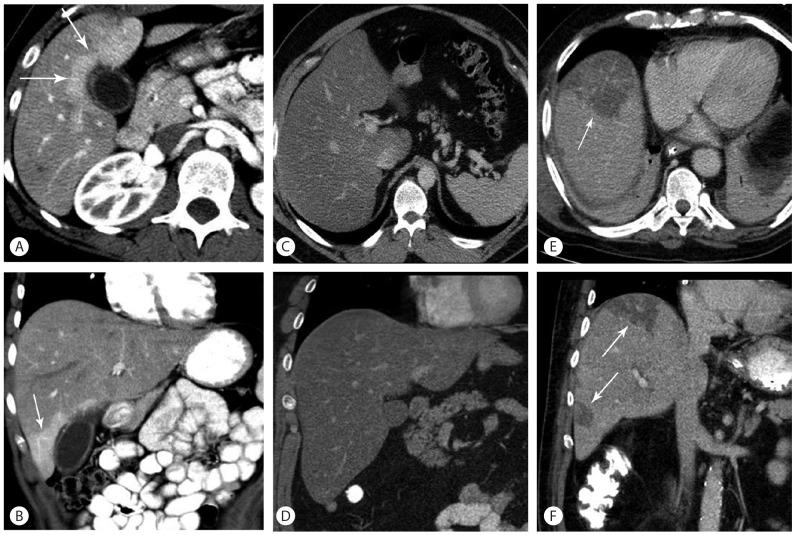

Treating patients undergoing chemotherapy who display findings of liver toxicity, requires a solid understanding of these medications. It is important for any clinician to have an index of suspicion for liver toxicity and be able to recognize it, even on imaging. Cancer chemotherapy has evolved, and newer medications that target cell biology have a different pattern of liver toxicity and may differ from the more traditional cytotoxic agents. There are several hepatic conditions that can result and keen clinical as well as radiographic recognition are paramount. Conditions such as sinusoidal obstructive syndrome, steatosis, and pseudocirrhosis are more commonly associated with chemotherapy. These conditions can display clinical signs of acute hepatitis, liver cirrhosis, and even liver failure. It is important to anticipate and recognize these adverse reactions and thus appropriate clinical action can be taken. Often times, patients with these liver manifestations can be managed with supportive therapies, and liver toxicity may resolve after discontinuation of chemotherapy.

治疗出现肝毒性表现的化疗患者,需要对这些药物有扎实的了解。任何临床医生都必须对肝毒性保持怀疑指数,并能够识别它,即使是通过影像学手段。癌症化疗已经发展,靶向细胞生物学的新型药物具有不同的肝毒性模式,可能与更传统的细胞毒性药物有所不同。有几种肝脏疾病可能由此引发,敏锐的临床及影像学识别至关重要。诸如窦性阻塞综合征、脂肪变性和假性肝硬化等病症更常与化疗相关。这些病症可表现出急性肝炎、肝硬化甚至肝衰竭的临床体征。预见并识别这些不良反应很重要,这样才能采取适当的临床行动。通常,有这些肝脏表现的患者可以通过支持性疗法进行治疗,并且肝毒性可能在化疗停药后消退。